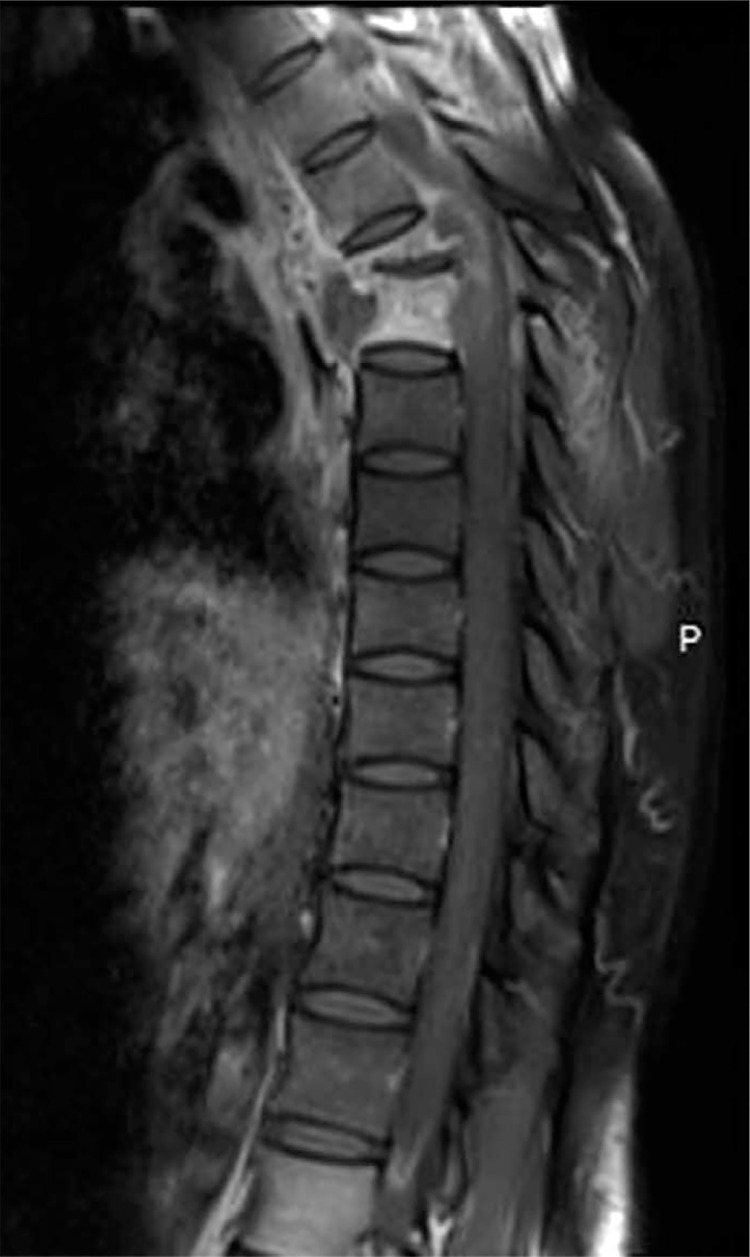

Results: The frequency in the Rheumatology Department of NTSCI was 2.94%, accounting for 104 patients. There were 68 men (65.38%), with a sex ratio of 1.88. The average age of the population was 57.91 years. All patients experienced back pain, with a lumbar location in 77 patients (74.04%). The average duration of the motor deficit was 2.97 months. A total of 3,532 patients were admitted to the conventional hospitalization unit of the Rheumatology Department at the CHU-B from March 1, 2017, to December 31, 2023. Among these, 104 patients had NTSCI, yielding a frequency of 2.94%. Spinal MRI was performed in 58 patients (55.77%), and the compression was extradural in 76.92% of cases (n = 80). The etiologies identified were Pott's disease in 32 patients (30.77%), followed by spinal metastases in 22 patients (21.15%). Twenty-nine patients (27.89%) experienced complications related to prolonged bed rest. No factor was significantly associated with the recovery of the motor deficit.

Conclusions: Non-traumatic spinal cord injury is relatively rare in rheumatological practice in Ouagadougou. The etiology is predominantly Pott's disease, which confirms the geographical distribution of NTSCI causes.